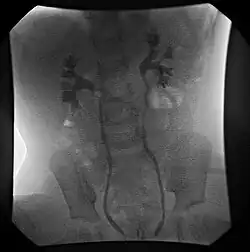

Vesicoureteral reflux (VUR) is graded according to severity.[1]

- Grade I – reflux into non-dilated ureter

- Grade II – reflux into the renal pelvis and calyces without dilatation

- Grade III – mild/moderate dilatation of the ureter, renal pelvis and calyces with minimal blunting of the fornices

- Grade IV – dilation of the renal pelvis and calyces with moderate ureteral tortuosity

- Grade V – gross dilatation of the ureter, pelvis and calyces; ureteral tortuosity; loss of papillary impressions